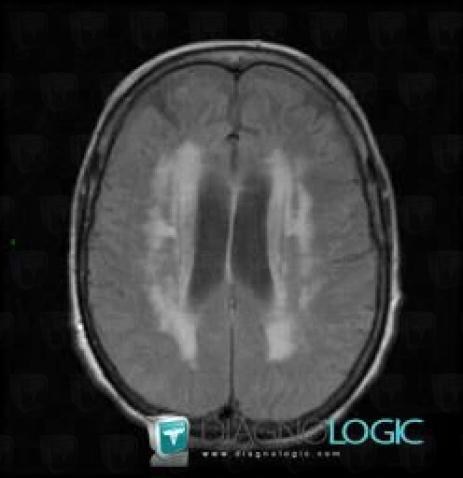

Schéma illustratif : Les lésions de substance blanche peuvent toucher différentes zones du cerveau, perturbant la transmission des informations entre régions cérébrales. Leur topographie et leur importance conditionnent symptômes et évolution.

L’échelle de Fazekas classe les lésions de substance blanche repérées à l’IRM selon leur localisation (autour des ventricules ou en profondeur) et leur importance. C’est un outil visuel : chaque stade correspond à un degré d’atteinte, allant de l’absence totale de lésions (0) aux atteintes sévères et diffuses (3). Cette graduation permet de prédire l’évolution potentielle de la leucopathie vasculaire mais, nuance capitale, elle ne prédit PAS tout : des patients avec score élevé peuvent encore évoluer lentement.

- Stade 3 : larges zones fusionnées et diffuses d’atteinte blanche cérébrale.

En stade 3, le diagnostic devient impossible à ignorer : les plages blanches fusionnent massivement à l’IRM, touchant toute la substance blanche cérébrale. Les symptômes deviennent fréquents et parfois handicapants : troubles cognitifs nets (planification, mémoire), difficultés motrices marquées, ralentissement global. L’impact sur la qualité — et parfois sur la durée — de vie devient majeur si rien n’est fait.